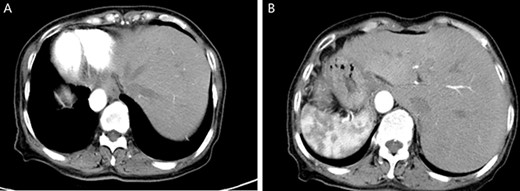

A physical examination revealed that the abdomen is flat, without gastrointestinal type and peristaltic wave, and the right lower abdomen has mild tenderness, with no rebound pain and muscle tension, and the mass can not be touched. Serum tumor markers were not elevated (CEA 2.3 ng/ml and CA-199 4.15 ng/ml). The laboratory examination confirmed mild anemia and hypoproteinemia. Abdominal computerized tomography (CT) showed the apex of the heart on the right side, the liver on the left side of the abdominal cavity (Fig. 1A), the stomach and spleen on the right side of the abdominal cavity (Fig. 1B), confirming SIT. In addition, the chest X-ray confirmed the apex of the heart on the right chest (Fig. 2A), and abdominal CT indicated that the tumor (stage T4N0M0) was located in the descending colon (Fig. 2B).

Enhanced CT of the upper abdomen showed that the heart was located on the right side of the thoracic cavity, the liver was located on the left side of the abdominal cavity (A), and the stomach and spleen were located on the right side of the abdominal cavity (B), confirming SIT.